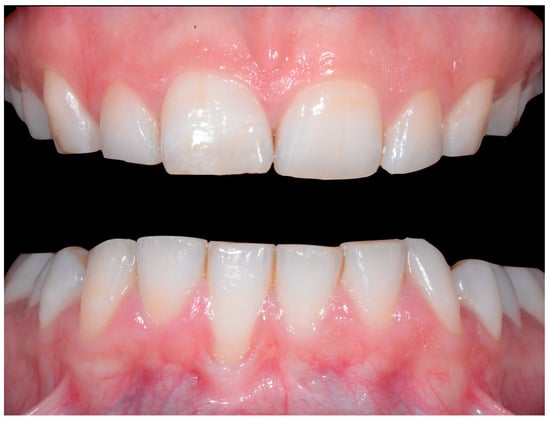

A 40-year-old patient presented with discomfort in tooth 31, citing past orthodontic treatment. As shown in Figure 11, the patient was in Class I and had poor oral hygiene associated with the presence of calculus in the incisivo-canine region. The root of 31, visible to its apex, was out of the bone and associated with severe gingival recession (Cairo RT2). Teeth 41 and 42 also showed gingival recession (Cairo RT2 and RT1).

Severe wire syndrome. Frontal and lateral views.

Figure 12 and Figure 13 show a difference in the height of the free edges of the mandibular incisors and the extent of root visibility of 31.

Severe wire syndrome. Frontal view.

Severe wire syndrome. Lateral views.

No retainer was present in the maxilla, only a residual mandibular retainer, still bonded to 32 and 42, was visible (Figure 14), as well as incisal crowding and a difference in the visibility of the buccal and root surfaces of 41 compared to the contralaterals. In this extreme clinical situation, a severe and terminal wire syndrome on tooth 41, the “X-effect” type, was observed.

Severe wire syndrome. Occlusal view.